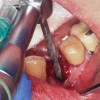

Prior to drilling the osteotomy, a landmark point on the patient scan was verified against direct visualization by placing the drill tip on the chosen anatomical landmark. Surgery proceeded under RADS guidance, in the form of auditory feedback (ie, mode-change and warning beeps) and haptic feedback (ie, resistance to drill motion) as well as visual guidance via a monitor (ie, navigation). To initiate the osteotomy, a 2.3-mm round drill was placed in the robotic guidance arm. As per the implant manufacturer's recommendations, three subsequent drills were used to perform the osteotomy in the prescribed location and angulation (Figure 4 and Figure 5). Implant placement was also achieved with the RADS system (Figure 6 and Figure 7).

Fig 4. Osteotomy into the extraction socket under robotic guidance.

Figure 4